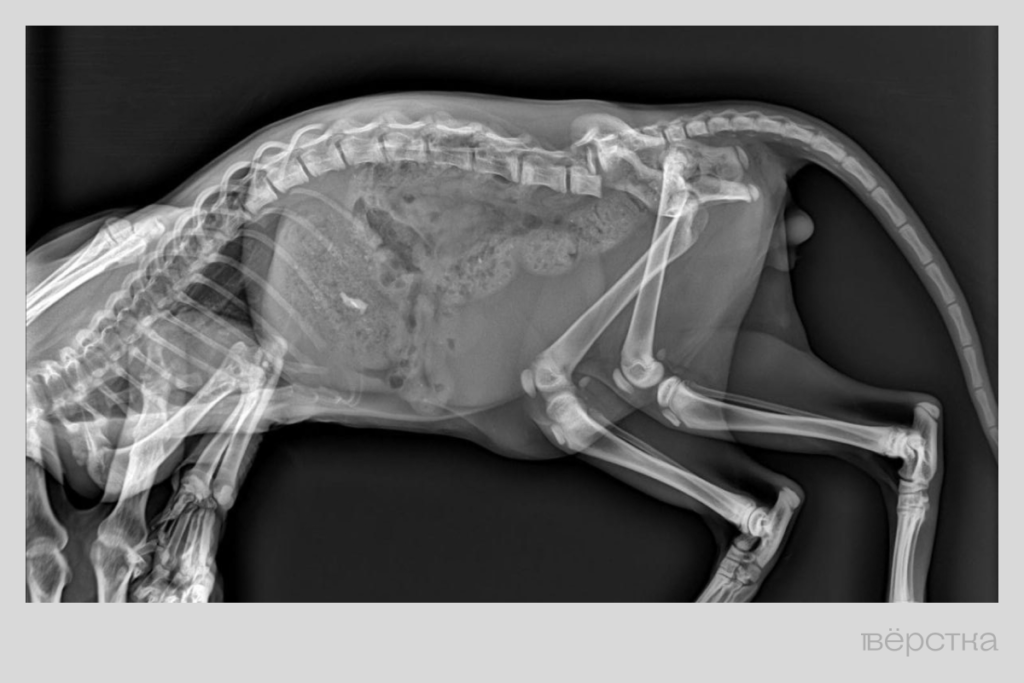

«Мы с соседкой вытащили его, а он хромат. Отвезли на рентген — оказалось, у него перелом позвоночника, — рассказывает Татьяна. — Местный хирург посмотрел на снимок и сразу сказал, что любые меры будут бесполезны».

Тогда снимок показали врачу из Москву. Сначала он ответил: «Тут ничего не сделаешь», но потом посмотрел на котёнка по видео и согласился попробовать помочь: увидел, что тот всё-таки ходит, хотя и подворачивает задние лапы, и хвост шевелится.

Рентгеновский снимок с Пушком. Снимок предоставлен Татьяной.